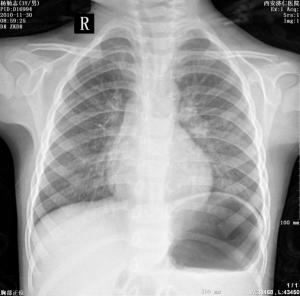

寇热是由贝纳立克次体(R.burnetii,又称伯氏立克次体、寇热立克次体)引起的急性传染病。1935年在澳大利亚首次发现,由于认为是一种原因不明的疾病(query为疑问之意),故名寇热。临床表现主要为突然发热,头痛及全身酸痛,呼吸道感染是主要传播途径。易引起肺部病变(寇热肺炎,Q-fever pneumonia)。一般在病程中无皮疹、外斐反应呈阴性,因而有别于其他立克次体病。